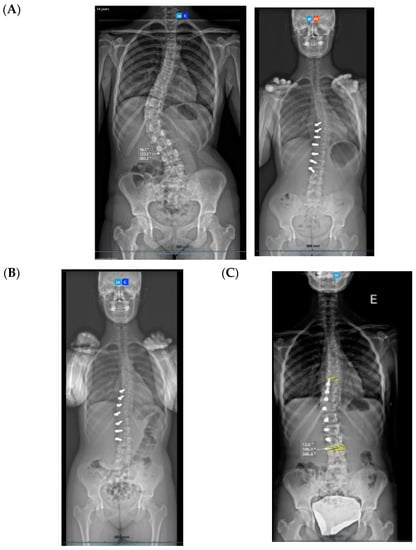

All three cases were thoracolumbar scoliosis (Lenke 5C) with an apex between T12 and L1 (Figure 3, Figure 4 and Figure 5).

Figure 3.

A 14-year-old adolescent. (A) Pre-op. (B) Immediate post-op. (C) One-year follow up.

Figure 4.

A 13-year-old adolescent. (A) Pre-op. (B) At 6-month follow up.

Figure 5.

A 14-year-old adolescent. (A) Pre-op. (B) At 6-month follow up.

As far as skeletal maturity is concerned, two cases were Sanders 3 (Risser 1 and 0) and one case was Sanders 5 (Risser 4).